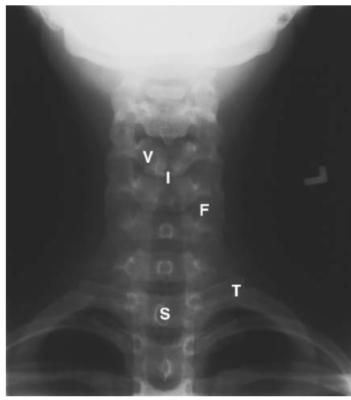

LIÊN HỆ HÌNH ẢNH HỌC

Cột sống cổ

Các chữ viết tắt:

- V = Vertebral body; thân đốt sống

- D = Intervertebral disc; đĩa gian sống

- Sc = Spinal cord; tuỷ sống

- S = Spinous process; mỏm gai

- N = Neural foramen; lỗ thần kinh

- P = Pedicle of vertebral arch; cuống cung

- I = Intervertebral disc space; khoảng đĩa đệm

- F = Facet joints; khớp diện nhỏ/facet

- T = T1 transverse process; mỏm ngang T1

Cột sống thắt lưng